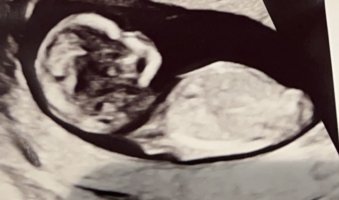

Synes jeg så antydning til NUB en gang bare, men fikk ikke bilde av det

Vet ikke om det er mulig å se noe på disse bildene: